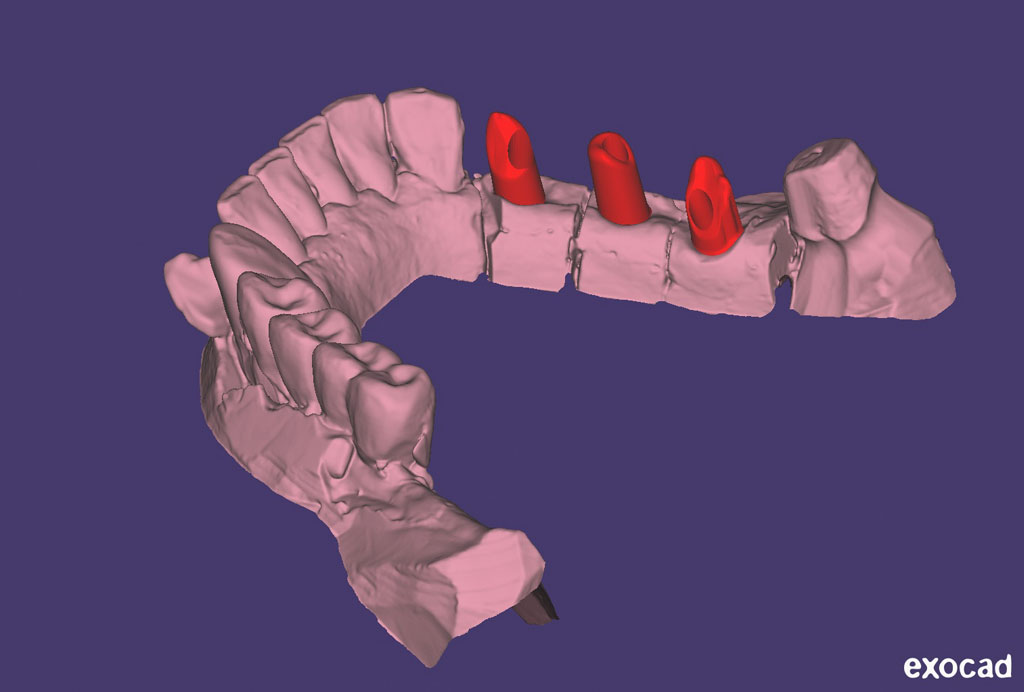

Fehlen in der Front oder im Seitenzahnbereich mehrere Zähne, ist eine Brücke oder Prothese vollkommen unnötig. Die fehlenden Zähne können entweder einzeln durch eine entsprechende Anzahl von Implantaten oder durch implantatgetragene festsitzende Brücken ersetzt werden. Das Bild der Kronen zeigt die drei Verschraubungen deutlich, im Mund liegen diese verdeckt am Gaumen oder im Bereich der Zunge.